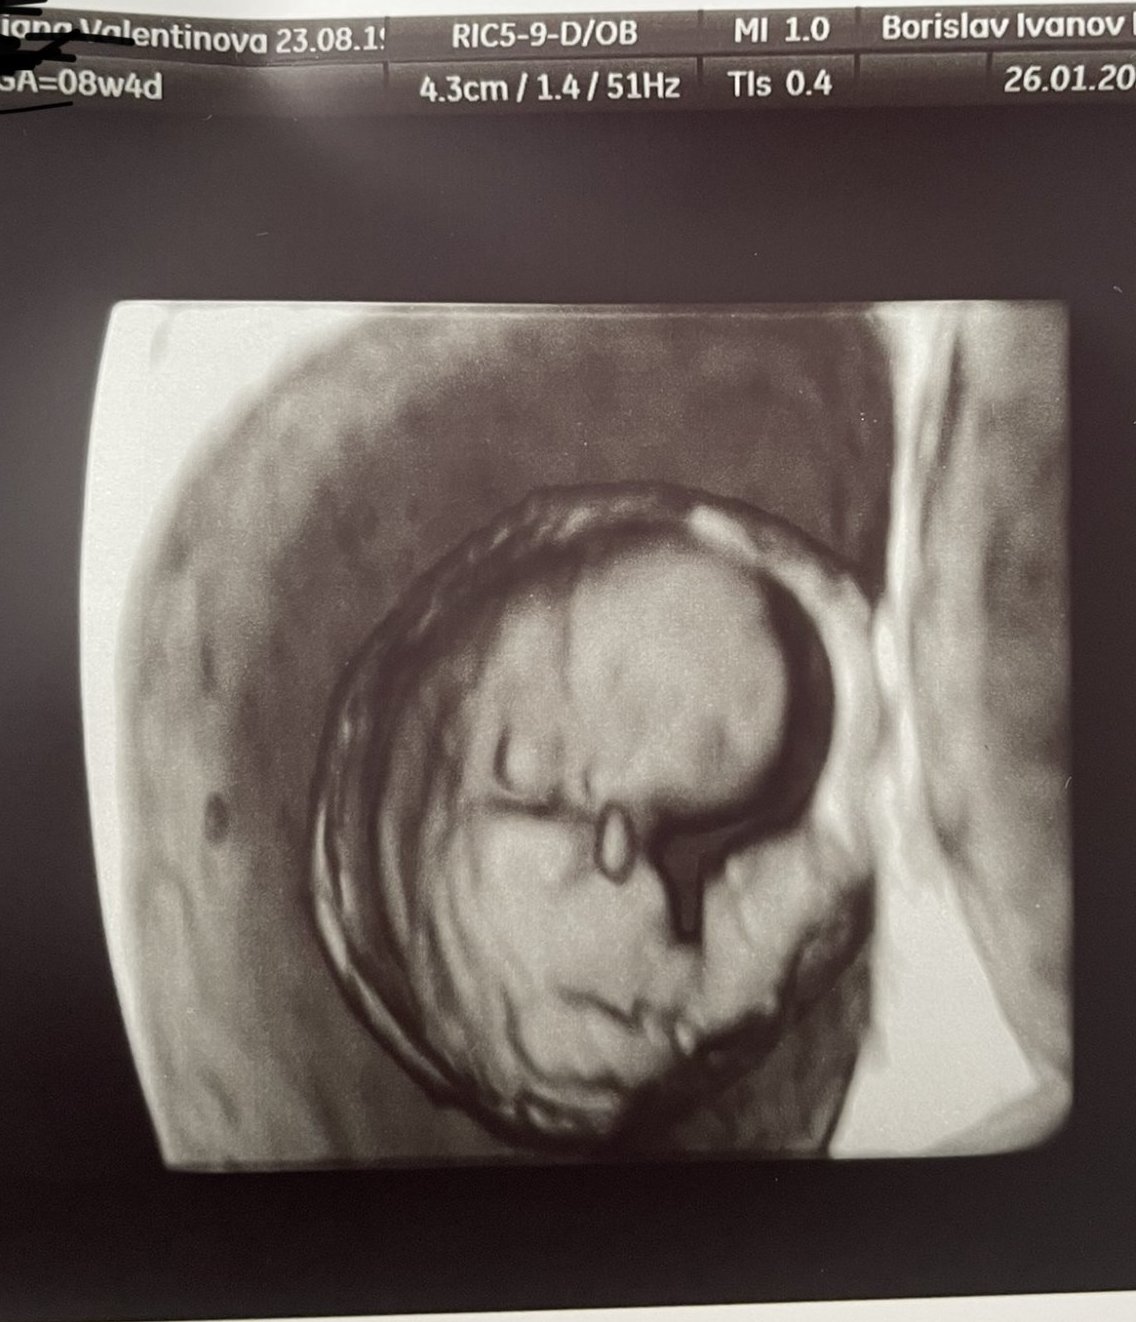

Терминът на бременността се определя въз основа на първия ден от последната менструация и обикновено не се променя, освен ако няма нередовен цикъл или други медицински причини. Измерванията на плода по време на ултразвукови прегледи могат да доведат до различни оценки, но те не променят официалния термин, който се определя чрез цикъла.

Ранната фетална морфология (ФМ), обикновено се извършва между 16-та и 18-та седмица от бременността, включва цялостно изследване на всички органи на бебето с помощта на ултразвук. От друга страна, биохимичният скрининг (БХС) се провежда между 11+0 и 13+6 седмици и включва вземане на кръвни проби и измервания с ехограф. Ранната фетална морфология се прилага, ако по някаква причина не е извършен ранният скрининг.

Промяната на термина на бременността може да се дължи на измерванията на бебето по време на ултразвуков преглед, които могат да доведат до различни термини, но те не променят официалния термин, който се определя от цикъла. В случай на нередовен цикъл или други медицински причини, терминът може да бъде коригиран от лекаря.